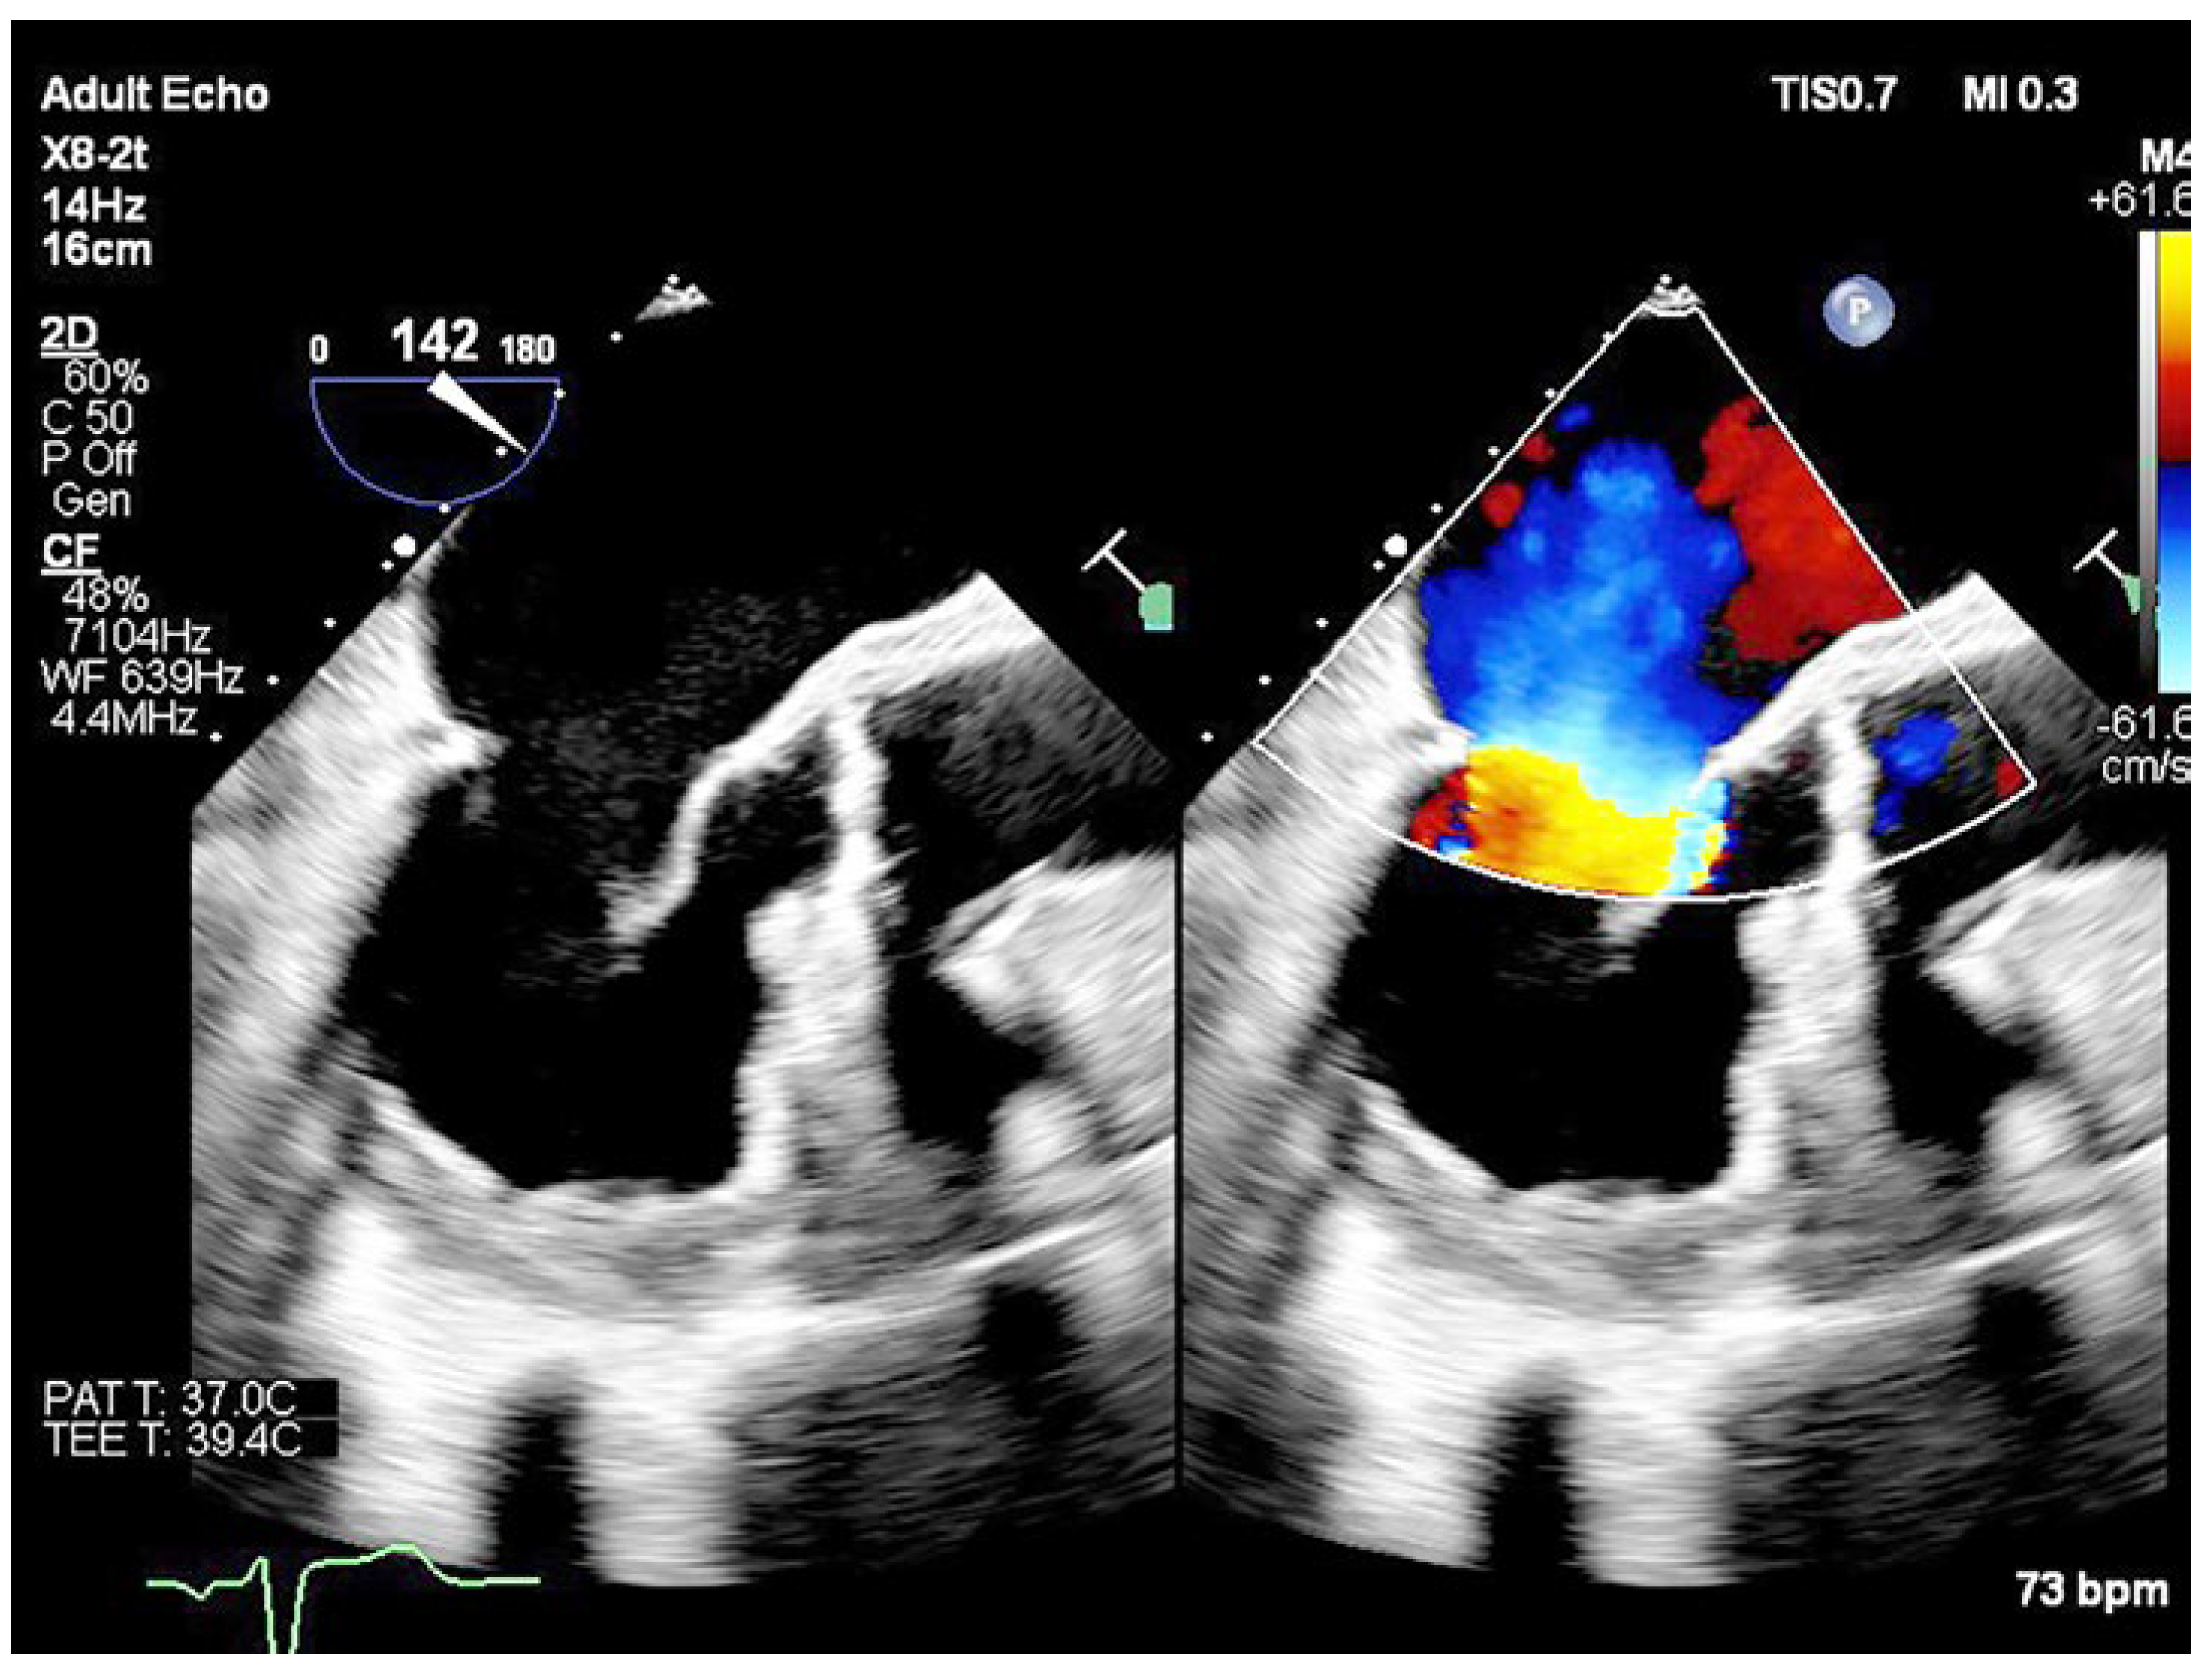

Case Description

Operative Procedure